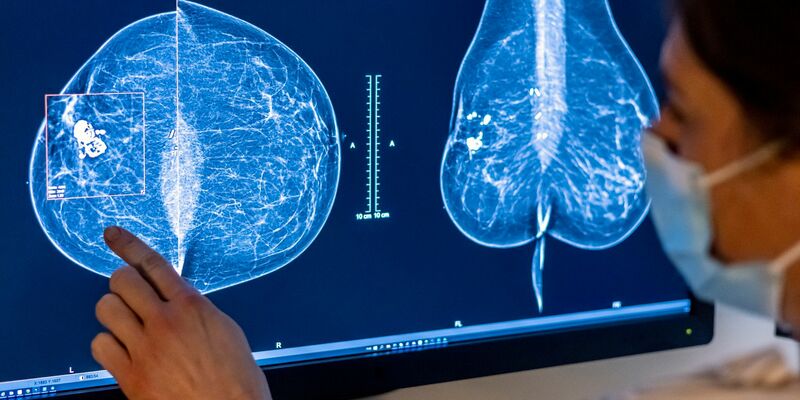

Frauen seien auch nicht genügend über die Krebs-Risikofaktoren Tabak, Alkohol, Adipositas (Fettleibigkeit) und Infektionen aufgeklärt. Zum Beispiel hätten 2019 in Großbritannien nur 19 Prozent der Frauen, die eine Mammografie für Brustkrebserkennung durchführen ließen, gewusst, dass Alkohol einer der größten Risikofaktoren für Brustkrebs ist.